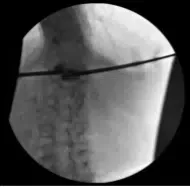

Imagen fluoroscópica

Atestiguo que fui el neurocirujano titular y que realicé todo este caso yo mismo con la ayuda de mi co-cirujano. Realizamos ambos aspectos de este caso por igual, operando de forma bipedicular, y supervisamos e interpretamos directamente todas las imágenes fluoroscópicas en conjunto.

Las radiografías finales de AP y laterales indicaron una excelente posición de metacrilato de metilo con extravasación mínima a superior del espacio discal T12-L1. En consecuencia, se retiraron las agujas introductoras de un solo toque Kyphon.